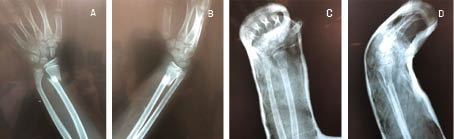

Clinical radiological evaluation of the use of a new device for the closed reduction of distal radio fractures

Distal radius fractures are frequent and represent 55% of the total in children and adults as well as 1.5% of the total emergency room visits. In children, 90% are managed with closed reduction and application of plaster; in adults, treatment varies according to type, experience of the doctor and general condition of the patient. In this setting, it is common for primary care to be delayed due to empirical events, causing significant inflammation and edema, which makes the closed reduction of the fracture difficult, causing the need for open reduction. The present work shows a steel device, designed for the closed reduction of distal radius fractures that was used in public hospitals in Navojoa, Sonora, Mexico. Thirty patients with displaced distal radius fracture with an evolution between one and seven days, from 2017 to 2019, were documented. Standard radiological measurements were performed before and after reduction, obtaining results of 96.66% of the cases with satisfactory alignment, and statistically significant difference between pre and post indices (p < 0.05). One case required surgical treatment for poor correction, no distal neurovascular complications caused by the reduction mechanism were documented. Biomechanical tests were performed on the device that showed advantages over the traditional thumb reduction technique. It is concluded that this device for the closed reduction of distal radius fractures is an effective tool and that it is possible to favor its use.

Figure 3